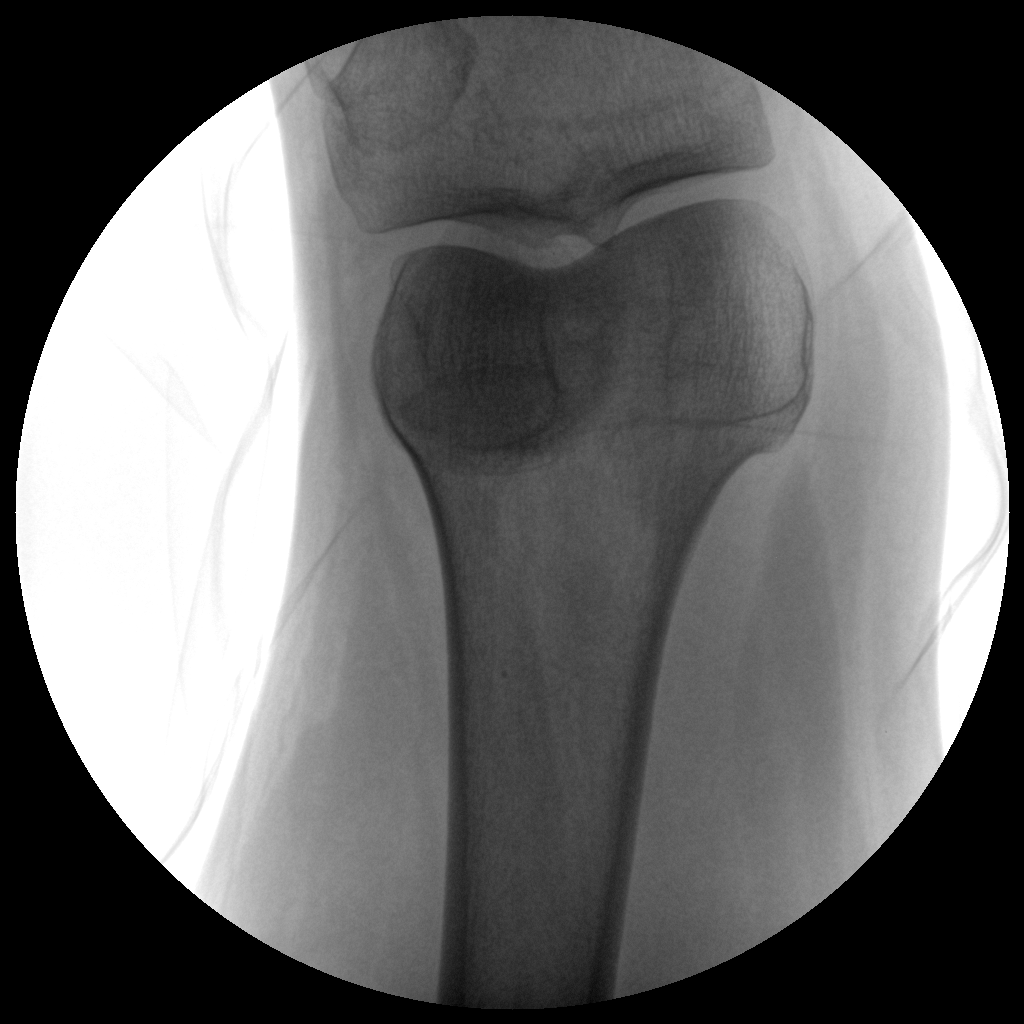

PLX112C 系列高頻移動式手術X射線機

●經(jīng)典圖文工作站,搭配雙監(jiān)雙控,操作更自如●全數(shù)字化百萬像素影像系統(tǒng),圖像清晰●獨特的電動輔助支撐臂設計, 臨床操作輕松自如●具備多種工作模式,滿足更多臨床需求●人體圖形化觸摸屏設計,操作方便快捷